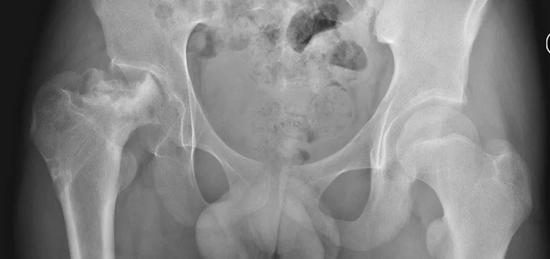

发育性髋脱位(Developmental Dysplasia of the Hip, DDH)是小儿骨科常见疾病,婴幼儿时期治疗后有些患儿会发生一过性股骨头血运障碍,出现股骨头骺的无菌性坏死,也是小儿骨科医生需要密切关注的问题。此类患者通常会表现为股骨头骨骺密度不均、碎裂吸收甚至消失,但随着时间推移,股骨头骺在血运重建后还能再次骨化塑型,但容易残留股骨近端发育异常,例如股骨头膨大、髋内翻、髋外翻、短颈畸形等,需要依据具体坏死类型并综合髋脱位情况进行针对性治疗。

▲左侧发育性髋脱位治疗后,半脱位合并股骨头缺血坏死表现